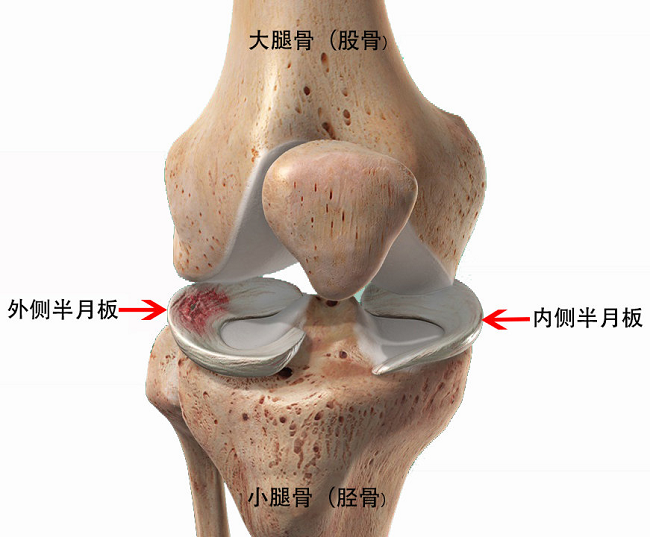

半月板是膝关节内一对具有缓冲减震、维持关节稳定、保护关节表面软骨的“垫片”。在正常情况下,能为膝关节提供缓冲和稳定支持作用。但损伤或膝关节炎会导致半月板撕裂,这将导致膝盖疼痛、肿胀和运动不利。半月板一旦损伤,尤其是外伤性损伤后,一定要到医院专科及时治疗。

半月板在股骨末端形成一个“环”状,可以在膝盖内微动,主要起到稳定关节和缓冲的作用,以减轻膝盖承受的重量和压力。

当半月板撕裂时,用于缓冲的环结构被破坏,半月板内纤维结构紊乱,滑液不断流失,表面变得毛糙、褶皱,甚至滑脱到关节内其他部位造成关节的绞索,引起膝关节的不适和疼痛。就如同鞋里坏掉的鞋垫卷曲皱褶,硌脚时间长了就会引起足部的肿胀和疼痛。